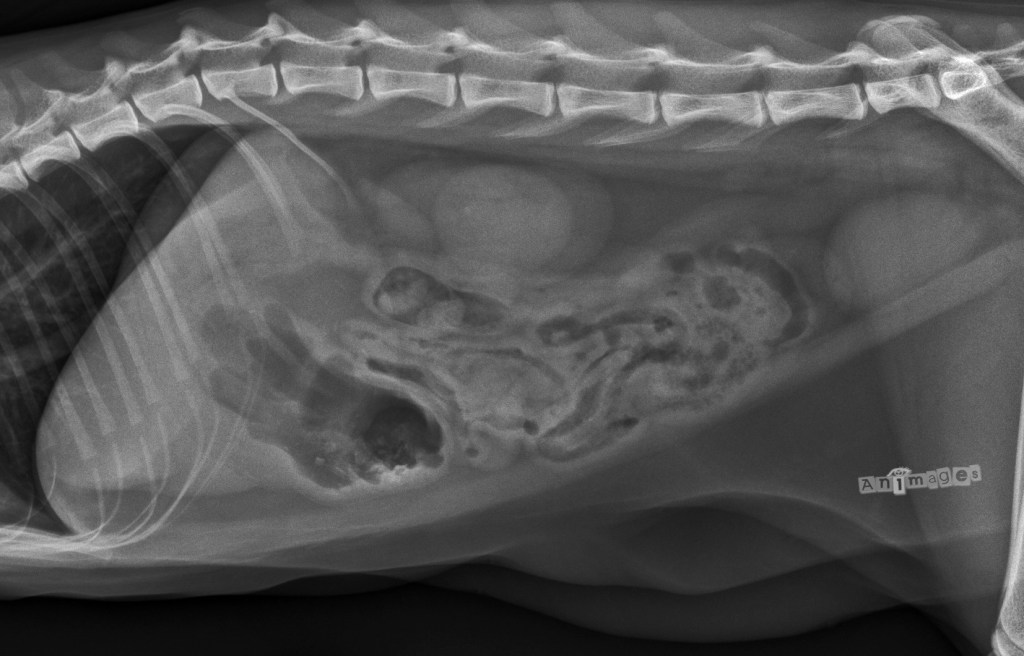

Latérale gauche